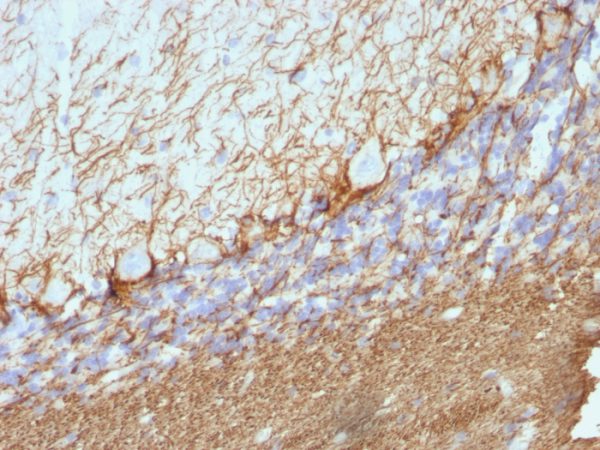

Formalin-fixed, paraffin-embedded Rat Cerebellum stained with Neurofilament Mouse Monoclonal Antibody (NE14).

This MAb reacts with a 200kDa protein, identified as heavy sub-unit of neurofilaments (NF-H). It reacts specifically with the phosphorylated KSP/KEP segment at the C-terminus of the heavy subunit (NF-H) of neurofilaments. After dephosphorylation of neurofilaments with alkaline phosphatase, this Ab no longer binds. Neurofilaments make up the main structural elements of axons and dendrites and are found in neurons, peripheral nerves, and sympathetic ganglion cells. Neurofilaments consist of three major subunits with molecular weights of 68kDa (NF-L), 160kDa (NF-M) and 200kDa (NF-H). Anti-neurofilament stains a number of neural, neuroendocrine, and endocrine tumors. Neuromas, ganglioneuromas, gangliogliomas, ganglioneuroblastomas, and neuroblastomas stain positively for anti-neurofilament. Neurofilaments are also present in paragangliomas as well as adrenal and extra-adrenal pheochromocytomas. Carcinoids, neuroendocrine carcinomas of the skin, and oat cell carcinomas of the lung also express neurofilament.